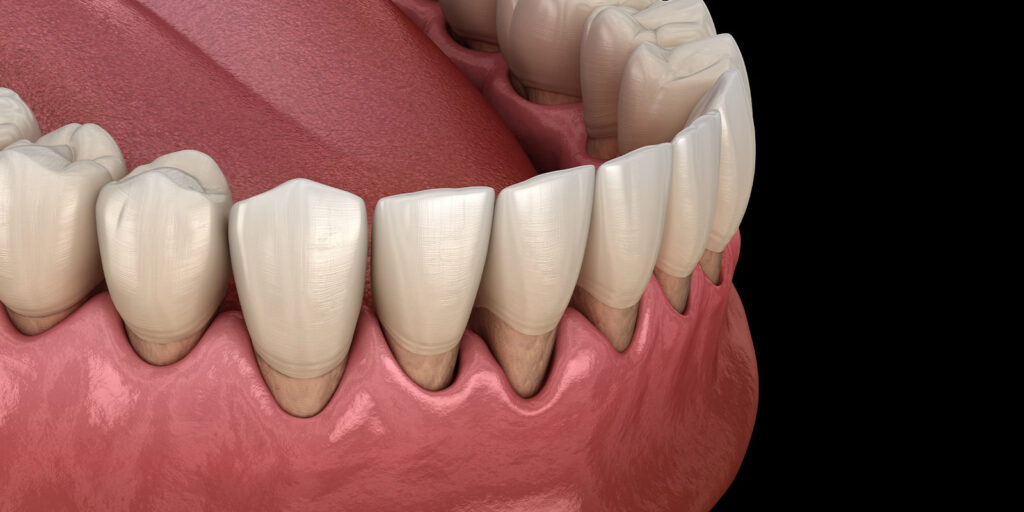

歯肉の退縮

歯肉の位置は加齢とともに少しずつ下がってきます。それに伴って歯の根っこが露出し、象牙質がむき出しの状態になります。このような象牙質表面では、歯ブラシが触れたり、温度変化などの刺激で痛みを感じることがあります。